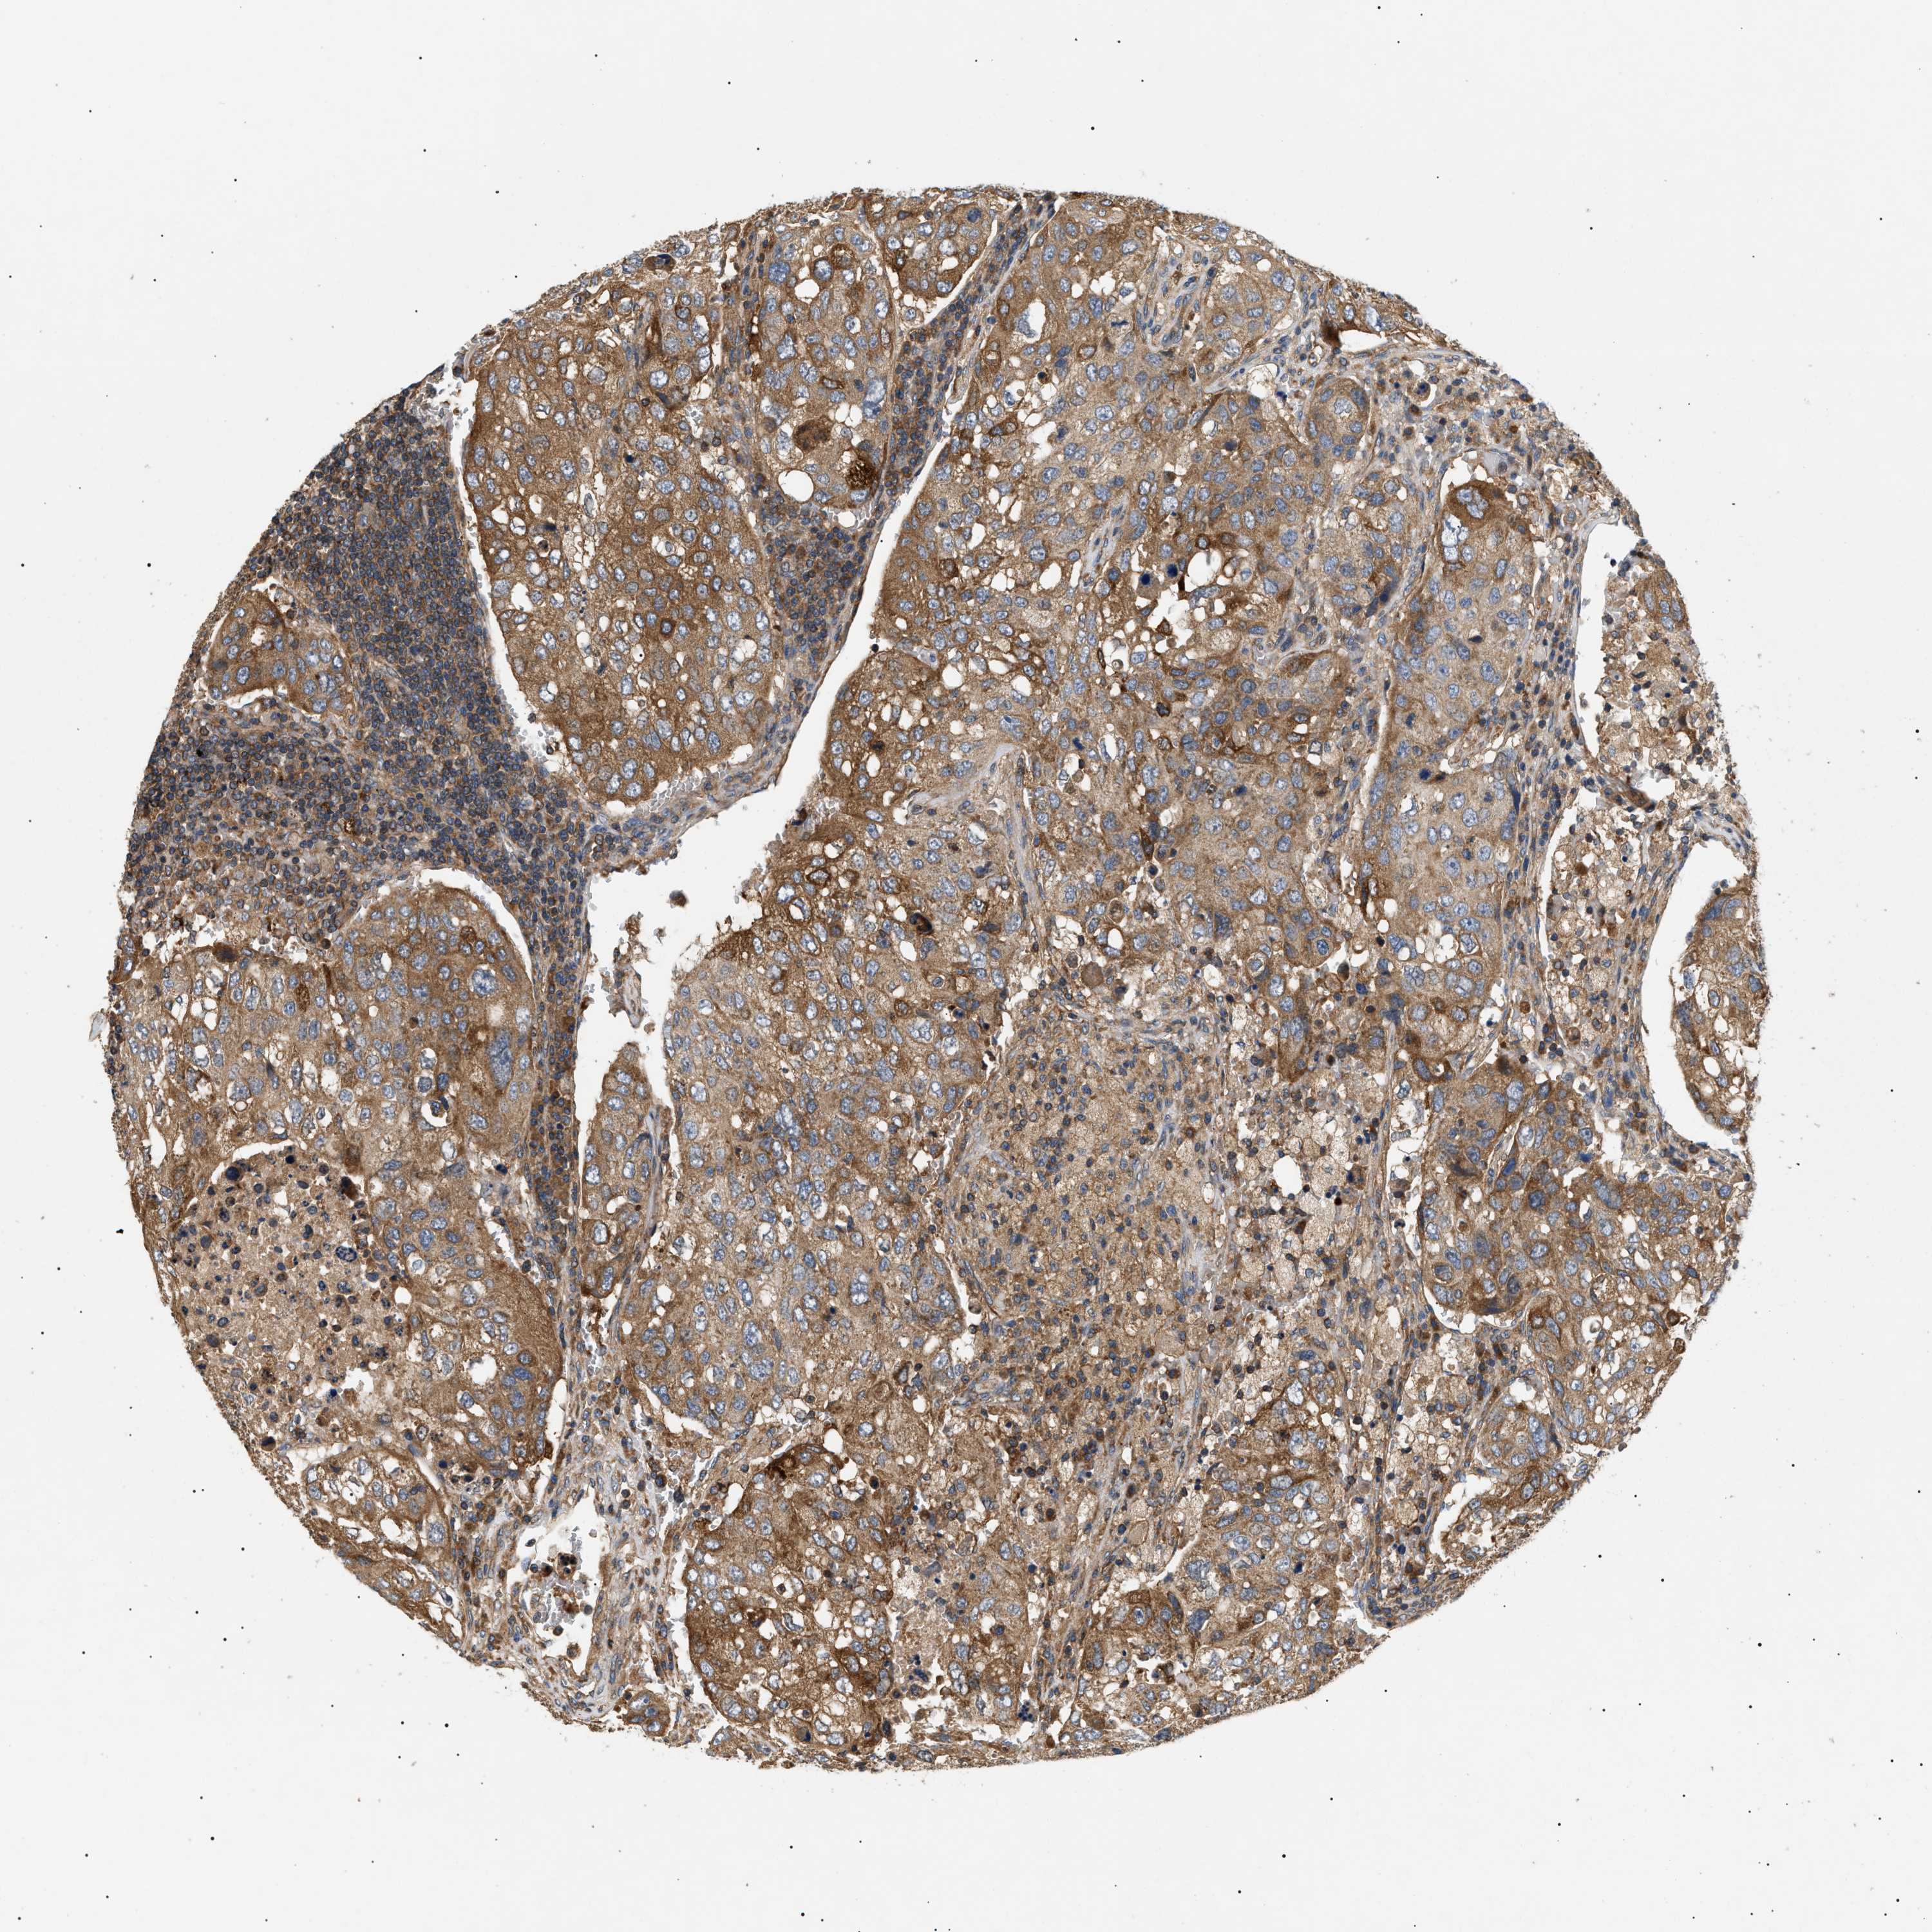

UROTHELIAL CANCER - Protein expressioni

A mouse-over function shows sample information and annotation data. Click on an image to view it in a full screen mode. Samples can be filtered based on level of antibody staining by selecting one or several of the following categories: high, medium, low and not detected. The assay and annotation is described here.

Note that samples used for immunohistochemistry by the Human Protein Atlas do not correspond to samples in the TCGA dataset.

Antibody stainingi

Antibody staining in the annotated cell types in the current human tissue is reported as not detected, low, medium, or high, based on conventional immunohistochemistry profiling in selected tissues. This score is based on the combination of the staining intensity and fraction of stained cells.

Each image is clickable and will lead to virtual microscopy that enables deeper exploration of all samples and also displays staining intensity scores, fraction scores and subcellular localization as well as patient and tissue information for each sample.

Antibody HPA016745

Staining

High

Medium

Low

Not detected

Intensity

Strong

Moderate

Weak

Negative

Quantity

>75%

75%-25%

<25%

None

Location

Nuclear

Cytoplasmic/membranous

Cytoplasmic/membranous,nuclear

Urothelial carcinoma, Low grade

Urothelial carcinoma, High grade